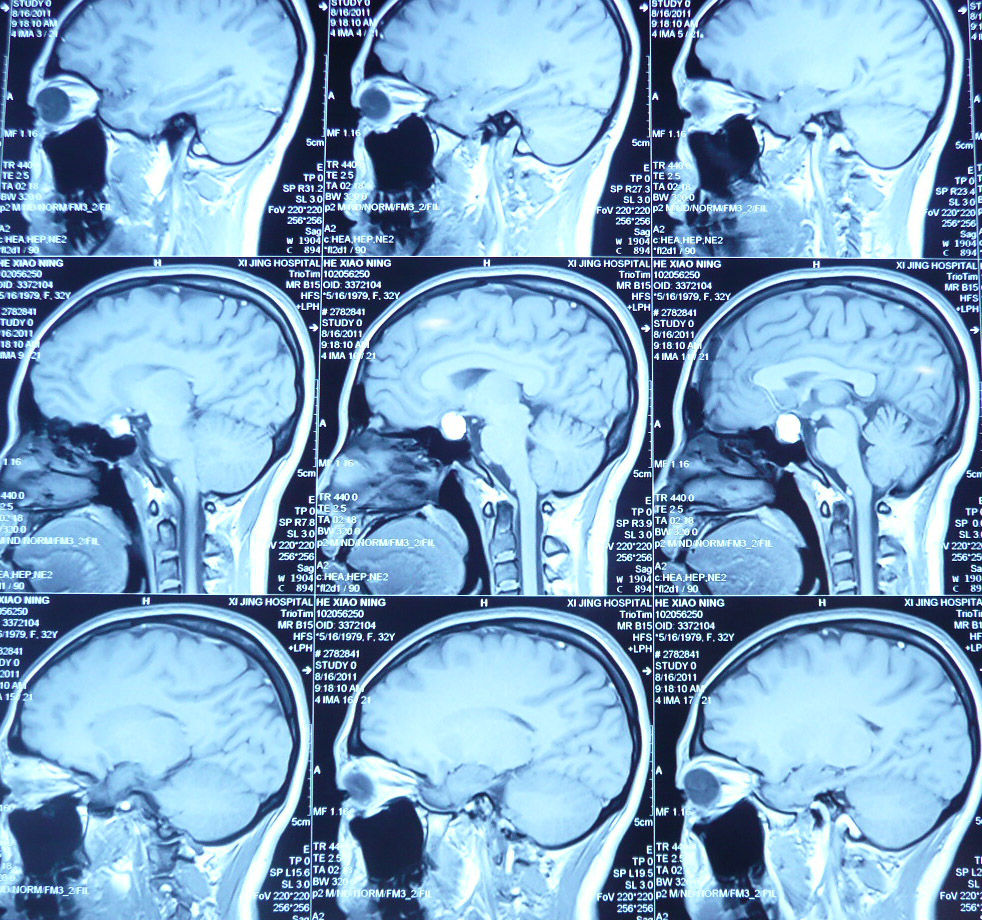

西京医院鞍区囊肿的手术治疗(实例)

贺晓生教授神经外科手术谈—"鞍上囊肿手术123"